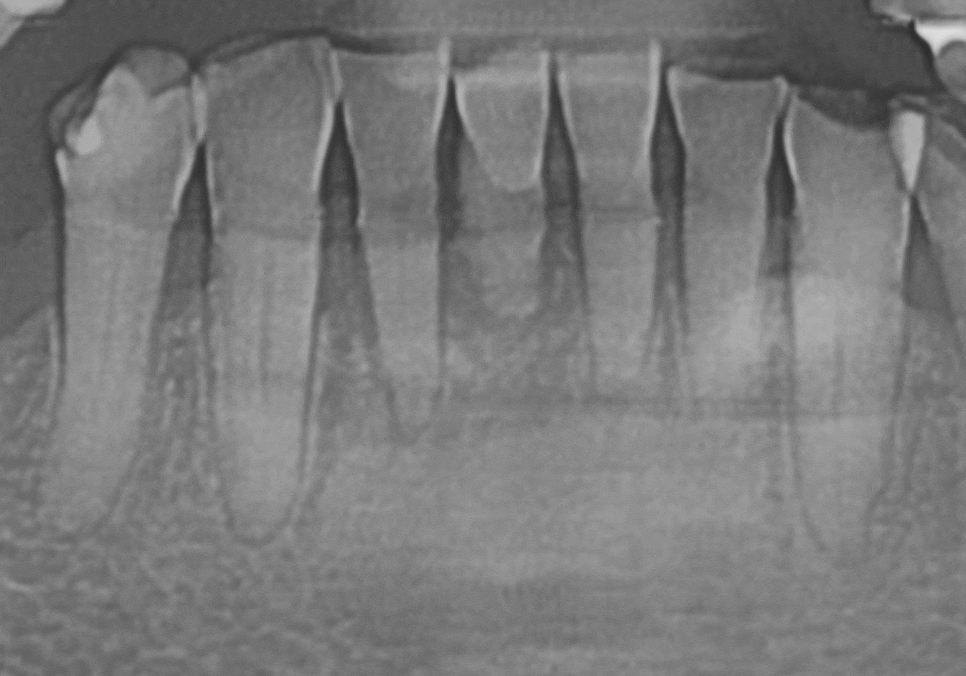

아래쪽 앞니들은 잇몸뼈가 많이 녹아 흔들리고 있어

총 4개의 치아를 발치하기로 했습니다.

다행히 남길 수 있는 앞니들은

마모가 심하긴 했지만 뿌리는 괜찮았기에

신경치료 후 총 6개의 치아를 연결하는

브릿지 치료를 계획했습니다.